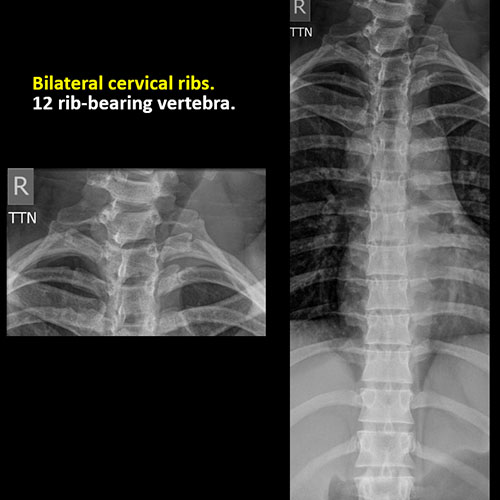

There are more or less than the expected 12 rib-bearing vertebral bodies. |

No | NA |

There are cervical ribs at the cervicothoracic junction, or hypoplastic or rudimentary ribs at the thoracolumbar junction. |